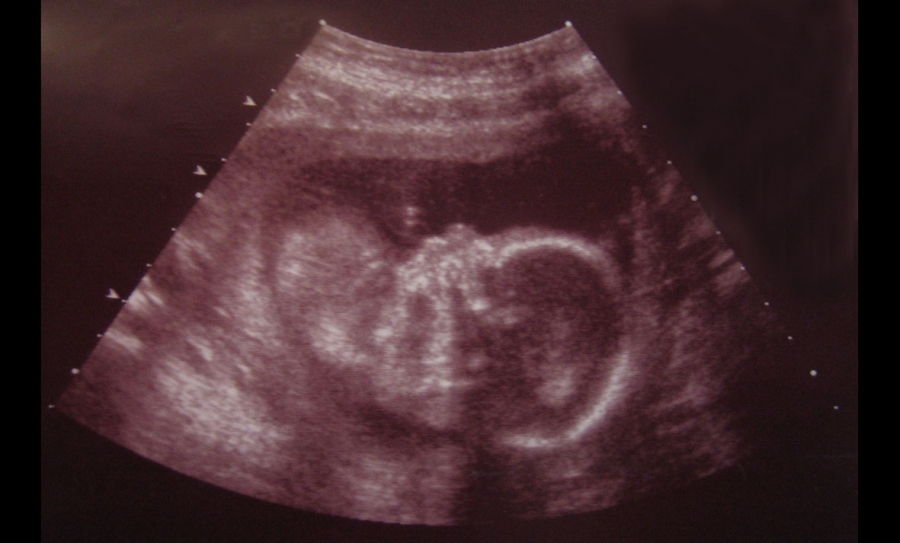

Επιστήμονες στις ΗΠΑ ανακάλυψαν ότι οι μικρές εναποθέσεις ασβεστίου στις μεμβράνες πέριξ των εμβρύων μπορεί να αποτελέσουν την αιτία για να «σπάσουν τα νερά» της εγκύου πριν την ώρα τους. Ο μηχανισμός αυτός πρόωρου τοκετού ήταν άγνωστός μέχρι σήμερα, αλλά μπορεί να ευθύνεται για αρκετές περιπτώσεις πρόωρης γέννησης μωρών.

Περίπου ένα στα δέκα μωρά γεννιέται πρόωρα, δηλαδή πριν την 37η εβδομάδα της κύησης, πράγμα που αυξάνει την πιθανότητα να εμφανίσει προβλήματα υγείας στο μέλλον.

Οι ερευνητές, που μελέτησαν πάνω από 100 πρόωρες κυήσεις, βρήκαν σε αρκετές περιπτώσεις ότι το αμνιακό υγρό περιέχει εναποθέσεις ασβεστίου, με συνέπεια οι εμβρυικές μεμβράνες να είναι λιγότερο ελαστικές και πιο εύκολο να σπάσουν.

Η νέα μελέτη δείχνει για πρώτη φορά ότι παρόμοια σωματίδια είναι δυνατό να παραχθούν και από το αμνιακό υγρό, με συνέπεια να αυξάνεται η πιθανότητα πρόωρης ρήξης της μεμβράνης (του αμνιακού σάκου) που συγκρατεί τα υγρά αυτά.